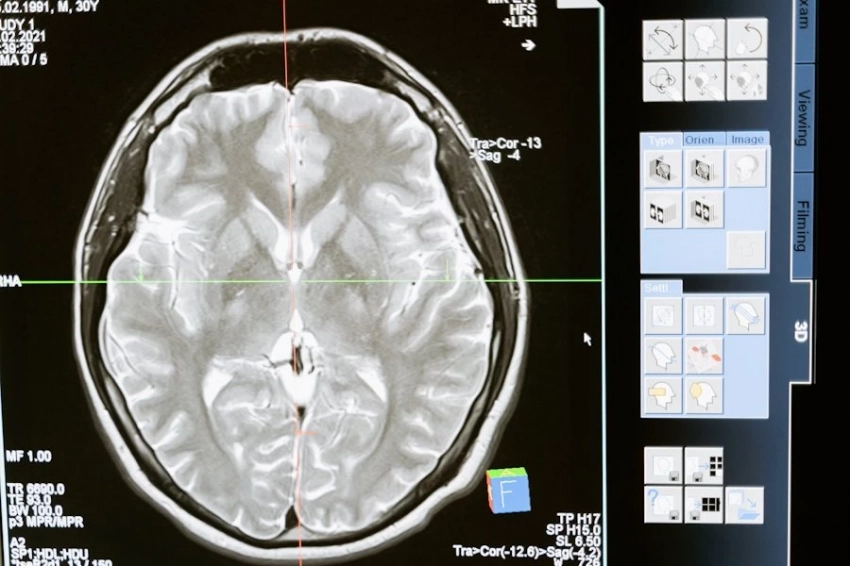

Рак мозга относится к самым сложным для лечения видам рака. Хирургия и химиотерапия рискованны, а лекарства не всегда могут попасть в мозг.

Чтобы обойти эти проблемы, ученые разработали «молекулярный GPS» для иммунных клеток, который направлял их с помощью «почтового индекса» для мозга и «почтового адреса» для опухоли.